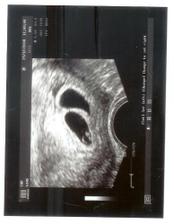

Vytoužené mimi . Vzhledem ke zdravotním problémům, operaci a věku mám za sebou IVF u Apolináře .Přes upozornění že napoprvé s tím raději nemáme počítat a šance že se uchytí obě není velká - čekáme dvojvaječná dvojčátka, která zatím ignorují tabulky a rostou stejně jako jedináčci. A vypadá to na kluka a holčičku. Děkuii všem u Apolináře a všem "snažilkám " za pomoc.